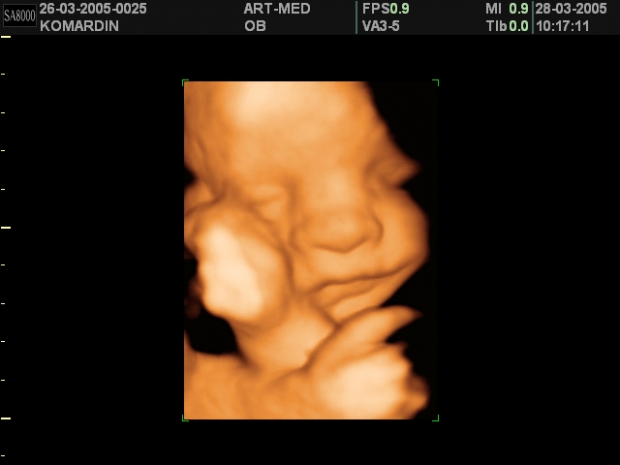

УЗИ: 14-ая неделя беременности

Плод достиг размера, сопоставимого с кулаком взрослого человека. На ультразвуковом исследовании, проведенном на 14-й неделе беременности, можно заметить, что все внутренние органы плода заняли свои окончательные позиции в брюшной полости, и больше не наблюдается выпячивания, как это происходило несколько недель назад. УЗИ уже позволяет различить даже узоры на ладошках малыша. Лицо начинает приобретать более четкие контуры, а длина шеи увеличивается. Плод активно сосет свои пальцы, что свидетельствует о развитии естественного рефлекса.